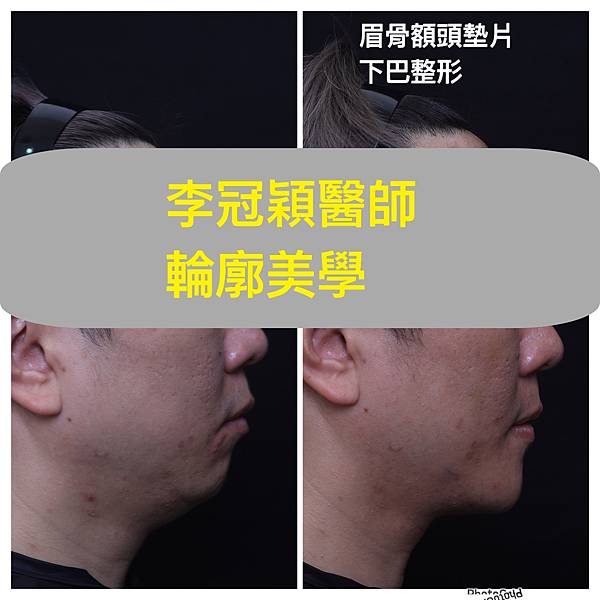

下圖:3D列印導航T區整形客製化墊片( 下巴/ 鼻/ 額眉骨/淚溝)

(男生範例)

輪廓在東方臉型是相當薄弱的一部分,只有整鼻子並不足以代表輪廓的到位,相反的只整鼻子可能會很突兀。下巴的後縮及過短在下臉部對於臉型平衡影響至大。

一張臉,除了對稱最重要的就是平衡,我們常聽到黃金比例或是應有比例,也就是表示臉部每一個部位都是有一定的相互角色達到平衡。下臉部的下巴,在東方人常常是後縮及過短,而且相對中臉顴骨較寬,所以往往失衡比例。因此東方臉型在整形手術中有一定比例的墊下巴或中臉削骨以達到平衡臉型。下巴短缺後縮,依程度不同而有不同的整形手術。